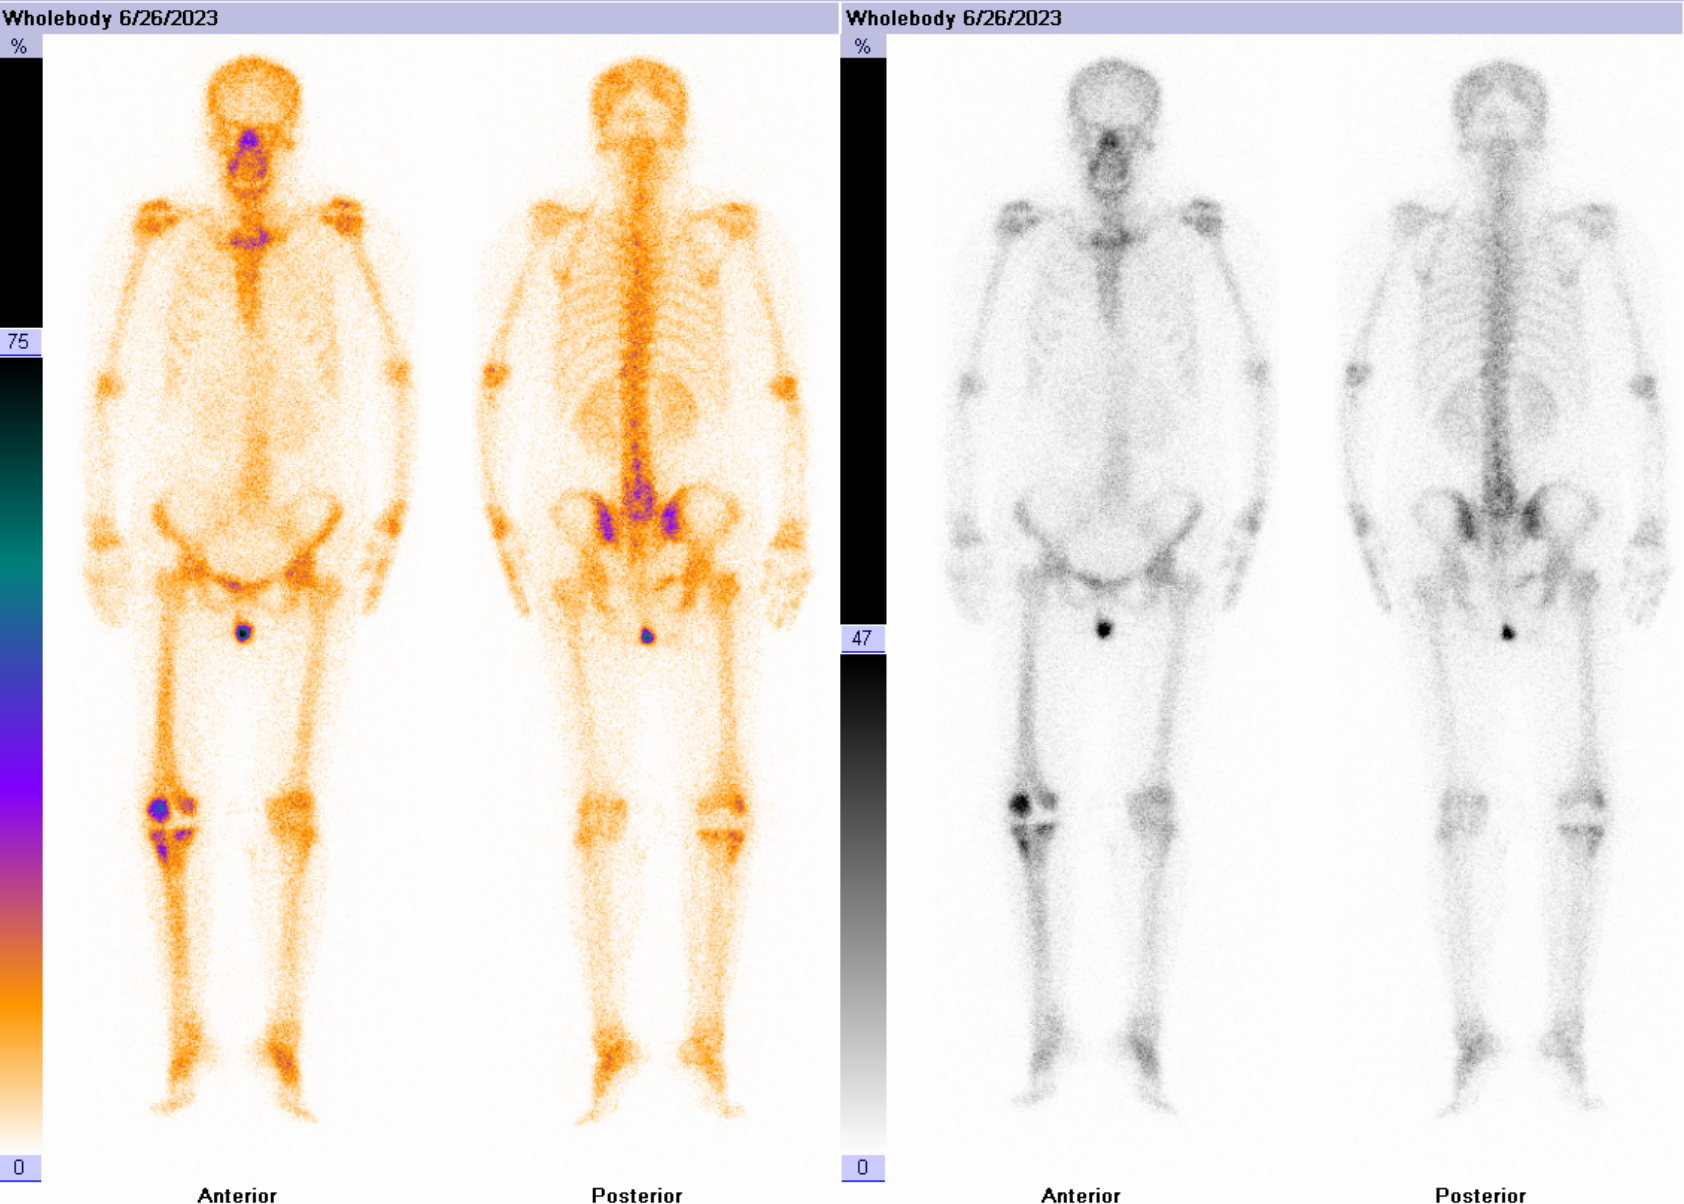

女性患者,1年前因“右膝关节炎”于当地医院行“右侧人工膝关节置换”手术治疗,术后康复良好。6个月前患者右膝关节疼痛、肿胀,于当地医院给予抗感染治疗,治疗后无明显好转,近期患者自觉症状持续加重,于我院就诊。入院后完善相关化验检查,血常规、C反应蛋白及血沉未见明显异常。

三相骨显像结果提示:右侧膝关节置换术后,三相骨显像血流相、血池相及延迟相均阳性,结合影像学特征考虑存在感染。

患者后续行手术治疗,术中见假体外侧脓性苔藓浸泡,培养出近平滑假丝酵母。

①假体周围感染:典型表现为血流相、血池相、延迟相显像剂明显异常浓聚、范围广且弥漫,同机CT常可见软组织影、骨质破坏等影像。